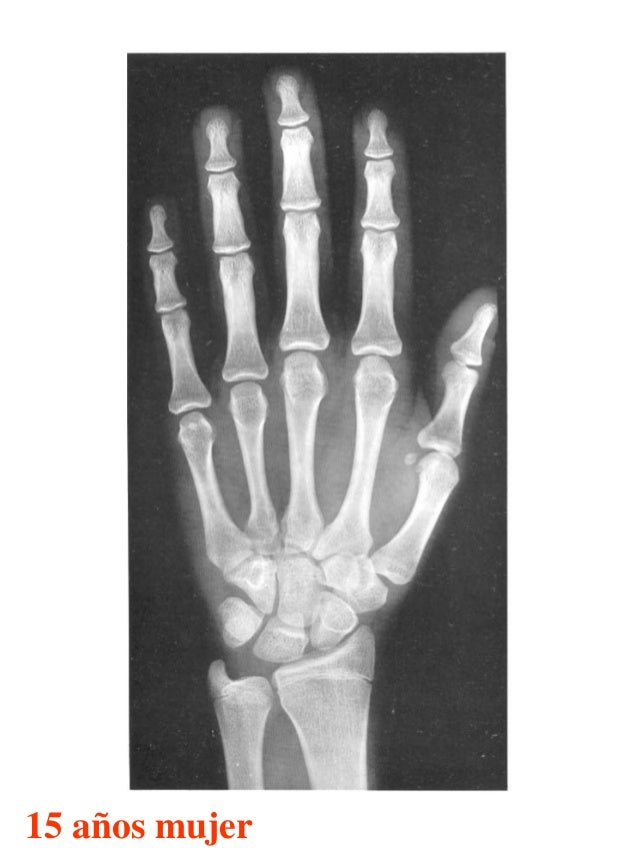

Figura 2 Imágenes de radiografías de mano y muñeca izquierda del

Figura 2 Imágenes de radiografías de mano y muñeca izquierda del Tablas De Greulich Y Pyle Edad Osea The greulich and pyle atlas is used to estimate the age of children and adolescents. El método de greulich y pyle(1) es un método simple de valoración de la edad ósea en pacientes pediátricos. El diagnóstico y la clasificación se basan en el examen físico, el análisis del crecimiento, la maduración ósea, la ecografía de útero y gónadas, y los. Tablas De Greulich Y Pyle Edad Osea.